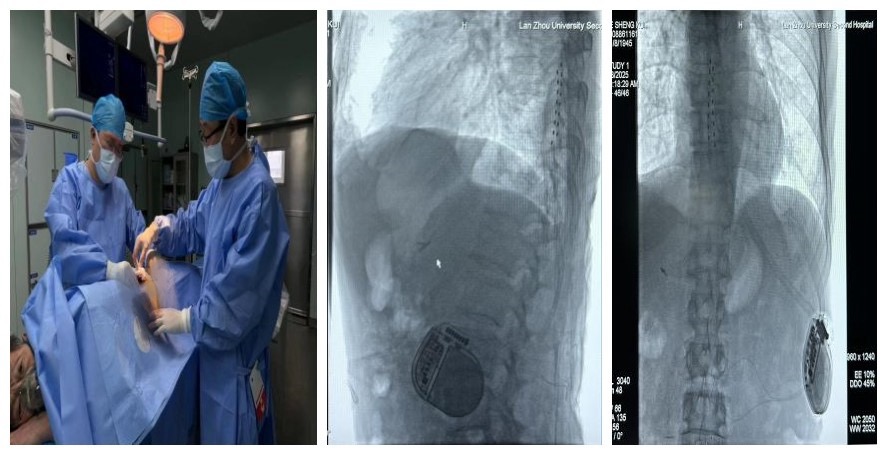

手术在疼痛科主任黄生辉和郭健主任的指导下,介入科及麻醉医师密切配合,郭刚、秦锐两位医生在DSA影像引导下进行。手术团队凭借精湛的技术操作,成功将电极精准植入患者硬膜外腔后间隙。

SCS是一种先进的神经调控技术,通过植入微电极至患者的脊椎椎管内,利用刺激器发出电脉冲信号,对脊髓背柱、脊神经根、背根神经节或周围神经进行刺激,从而调节神经功能,达到缓解疼痛的效果,具有微创、可逆的特点。SCS作为一种新型疗法,其适应症广泛,包括带状疱疹后神经痛、糖尿病周围神经血管性病变、动脉缺血、闭塞性病变、脊髓损伤、癌痛等顽固性疼痛。